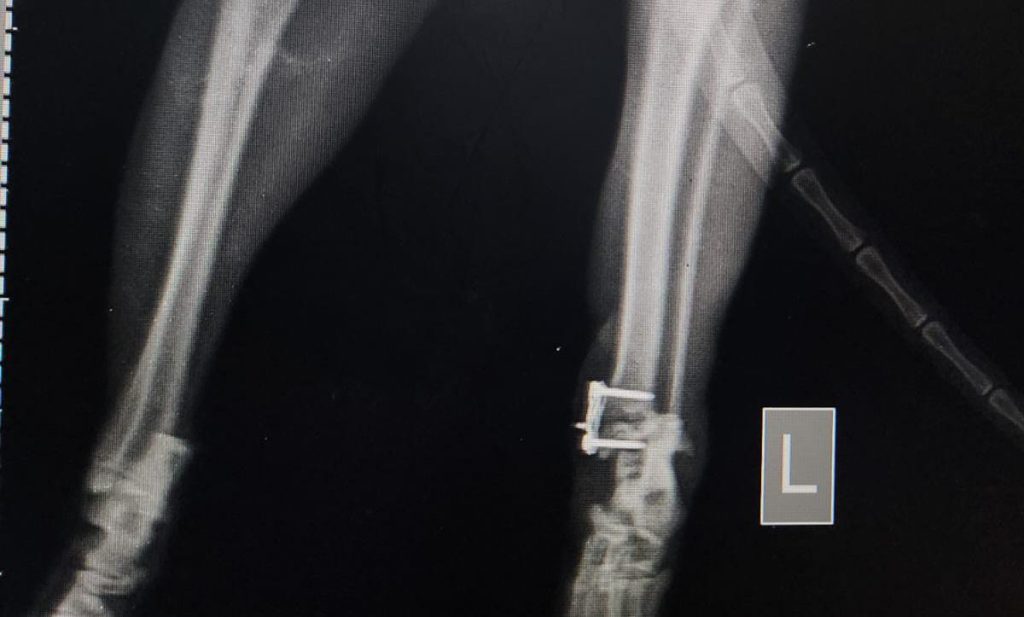

Si manis dipasang pen.

Si Manis kita temuin patah kakinya di akhir tahun 2025 dan udah dua kali di operasi dan dipasang serta dibuka pen-nya di petsmiledoknyom.jkt.